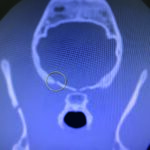

CT scan of skull is preferred for evaluate bone fractures and identify areas of acute hemorrhage or edema. CT scan showed multiple sites of skull fractures, right maxilla, both frontal, right zygomatic, right caudal mandible, right caudal zygomatic, right temporal, left occipital bone (Figure 3) and patchy small area of hyper-attenuation at the cranial of midbrain in pre-contrast study (Figure 4), no detectable mass effect, hypo-attenuated of large edematous parenchyma in the brain, right temporomandibular joint is displacement (Figure 5) and left tympanic bulla shows partial ventral fluid-filled.

Figures 4.1, 4.2

Patchy small area of hyper-attenuation at the cranial of midbrain in pre-contrast study.